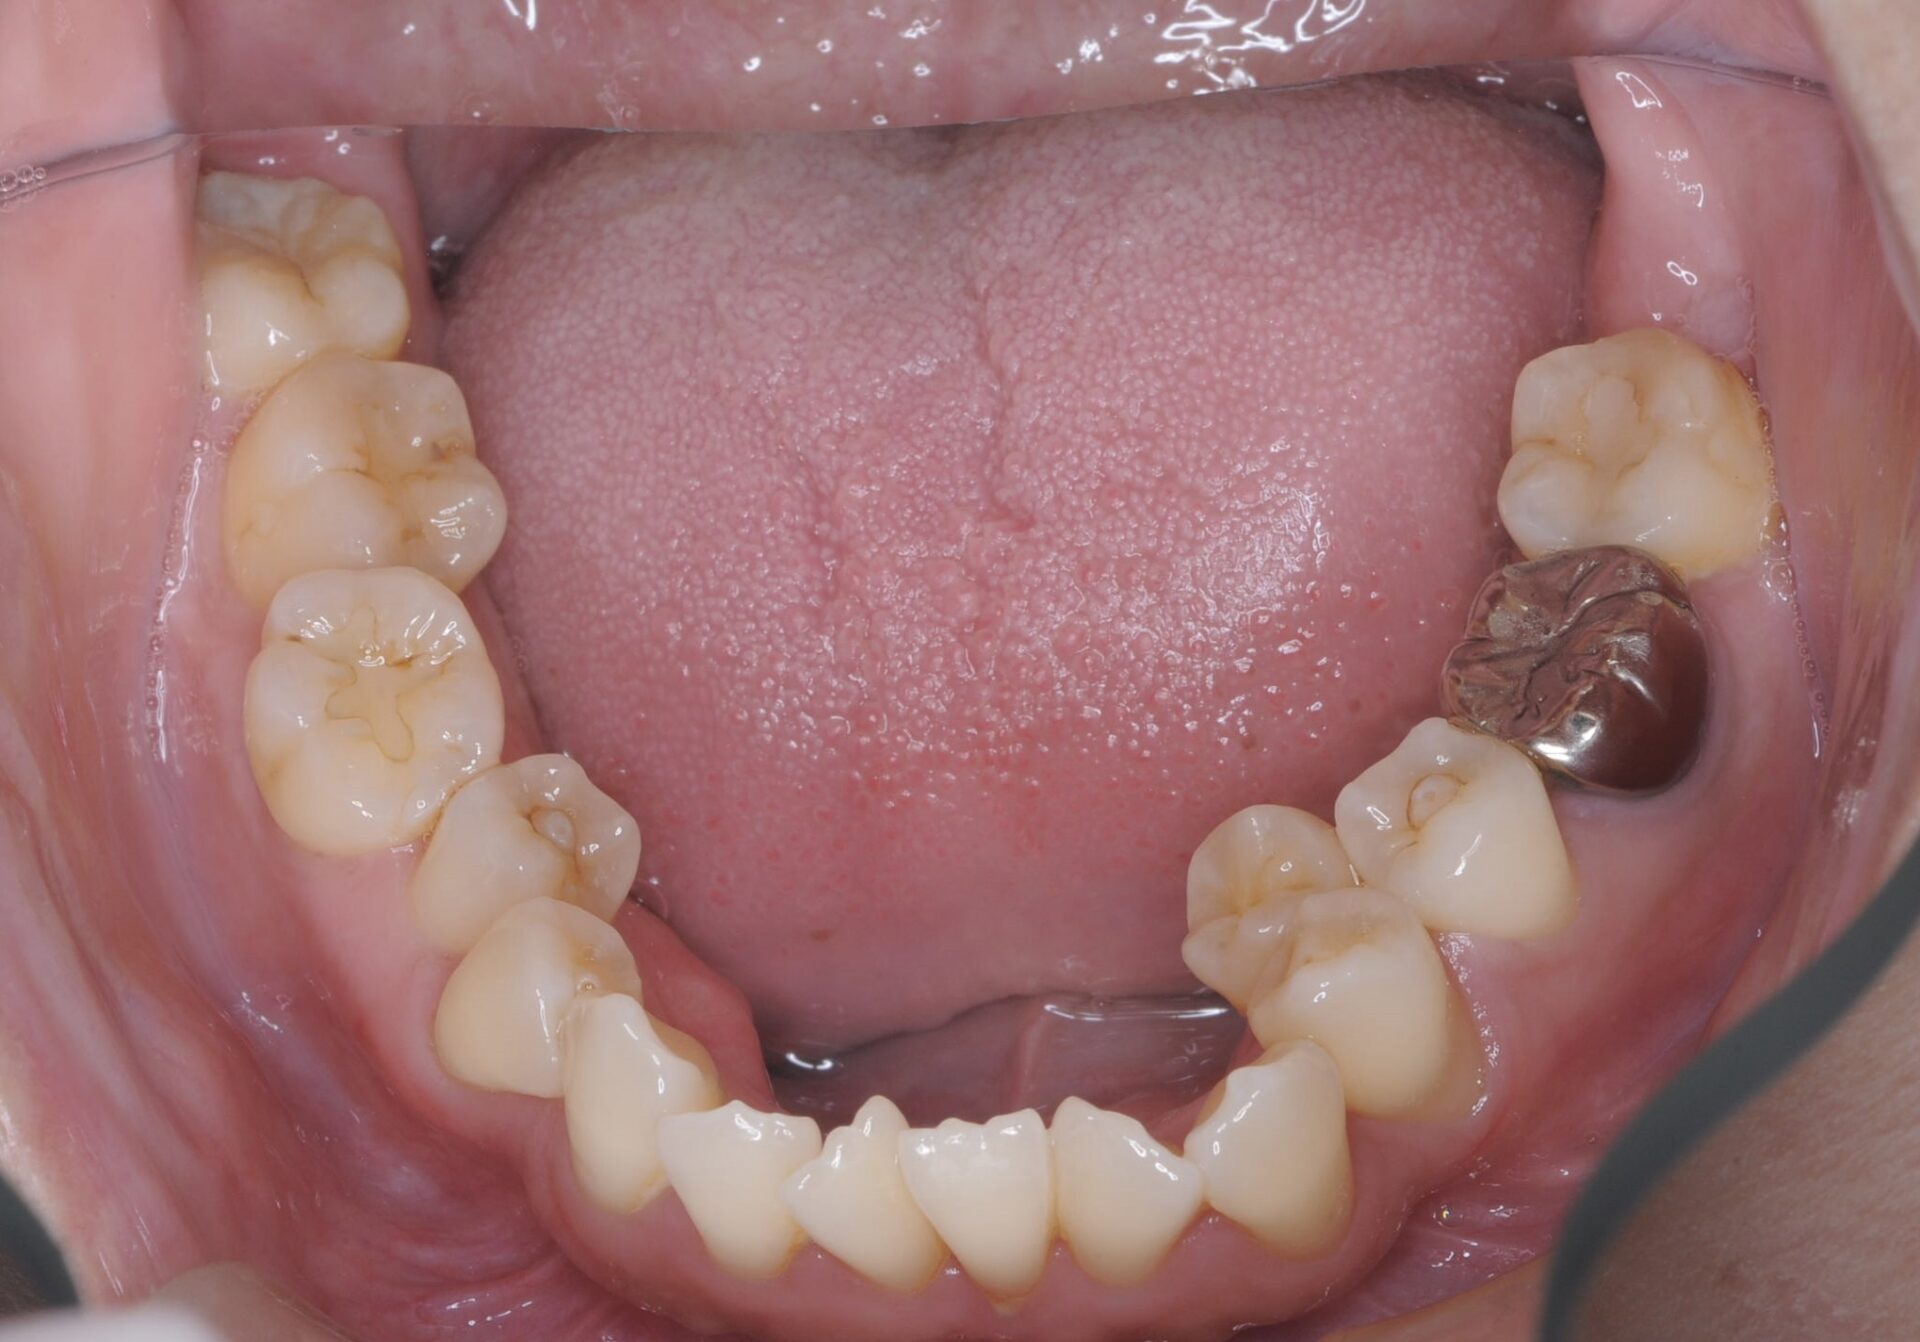

メインテナンス時(下顎)

矯正治療終了後メインテナンス時。

感染が取れ、過度な咬合力がかからなければ歯槽骨も回復してくる。動揺もなくなる。